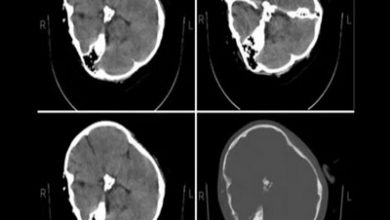

بیانیه متخصصان رادیولوژی درباره سی تی اسکن مهسا امینی

آکام نیوز: متخصصان نرورادیولوژی هیأت بورد رادیولوژی وزارت بهداشت در پاسخ به استعلام ریاست سازمان نظام پزشکی درباره تصاویر «سی…